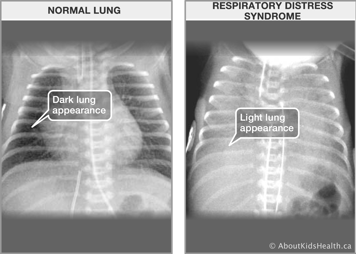

A chest X-ray will confirm the diagnosis in a premature baby with signs and symptoms of breathing difficulties. The X-ray often shows:

- small lung volume

- air bronchograms or air in the airways of the lung that are black in comparison to the surrounding white areas that do not contain air

- granular-looking areas on the lung where the lung resembles white salt and black pepper being sprinkled on the film. The more pepper, the more aeration; the more salt, the more collapse or fluid.